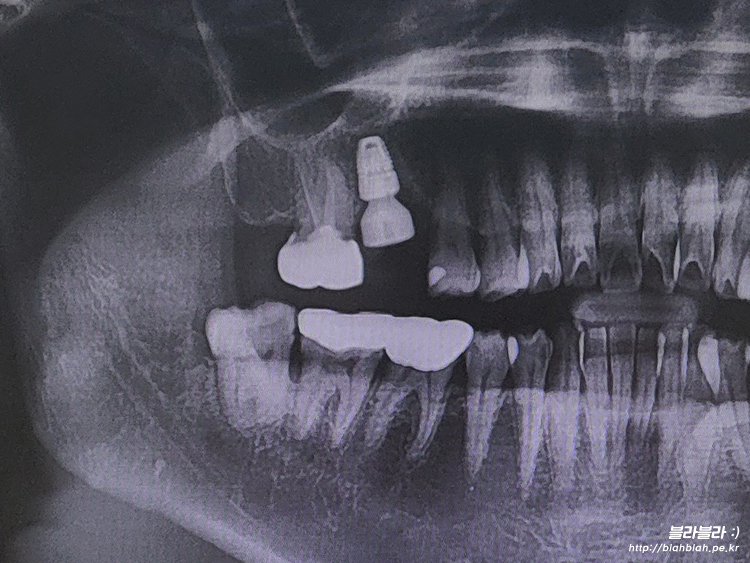

30대에 임플란트 시작 ㅠ_ㅜ

치아관리 제대로 못한 결말은

결국 30대에 임플란트...

이걸 또 언제 마무리하고

반대편치아를 또 시작해야하는건지... ㅠ_ㅜ